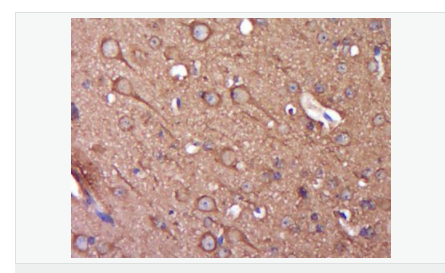

產(chǎn)品應用WB=1:500-2000 ELISA=1:5000-10000 IHC-P=1:100-500 IHC-F=1:100-500 Flow-Cyt=1ug/Test IF=1:100-500 (石蠟切片需做抗原修復)

Synuclein 包括α-Synuclein,β-Synuclein 和γ-Synuclein 是神經(jīng)細胞中富含的前突觸蛋白。α-Synuclein,Alzheimer’(AD)病淀粉樣蛋白沉積的成份之一,集中分布在神經(jīng)細胞的包體和突觸。在帕金森病人中發(fā)現(xiàn)有α-Synuclein的變異型,而γ-Synuclein與軸突病理學有關。此抗體將為Lewy小體癡呆癥、Parkinson癥、AD和其它一些神經(jīng)性疾病提供有用的病理診斷。